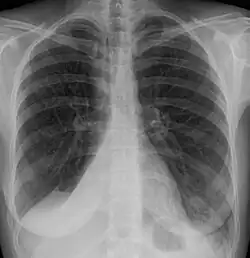

| Atelectasis of a person's right lung | |

Atelectasis is the partial collapse or closure of a lung resulting in reduced or absence in gas exchange. It is usually unilateral, affecting part or all of one lung.[2] It is a condition where the alveoli are deflated down to little or no volume, as distinct from pulmonary consolidation, in which they are filled with liquid. It is often referred to informally as a collapsed lung, although more accurately it usually involves only a partial collapse, and that ambiguous term is also informally used for a fully collapsed lung caused by a pneumothorax.[1]

Clinically significant atelectasis is generally visible on chest X-ray; findings can include lung opacification and/or loss of lung volume. Post-surgical atelectasis will be bibasal in pattern. Chest CT or bronchoscopy may be necessary if the cause of atelectasis is not clinically apparent. Direct signs of atelectasis include displacement of interlobar fissures and mobile structures within the thorax, overinflation of the unaffected ipsilateral lobe or contralateral lung, and opacification of the collapsed lobe. In addition to clinically significant findings on chest X-rays, patients may present with indirect signs and symptoms such as elevation of the diaphragm, shifting of the trachea, heart and mediastinum; displacement of the hilus and shifting granulomas.[13]